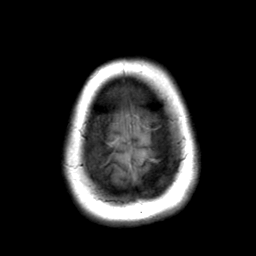

Cerebral hemorrhage, MR Study mr-t1 -- Slice #22

[Home][Help][Clinical] Slice 22